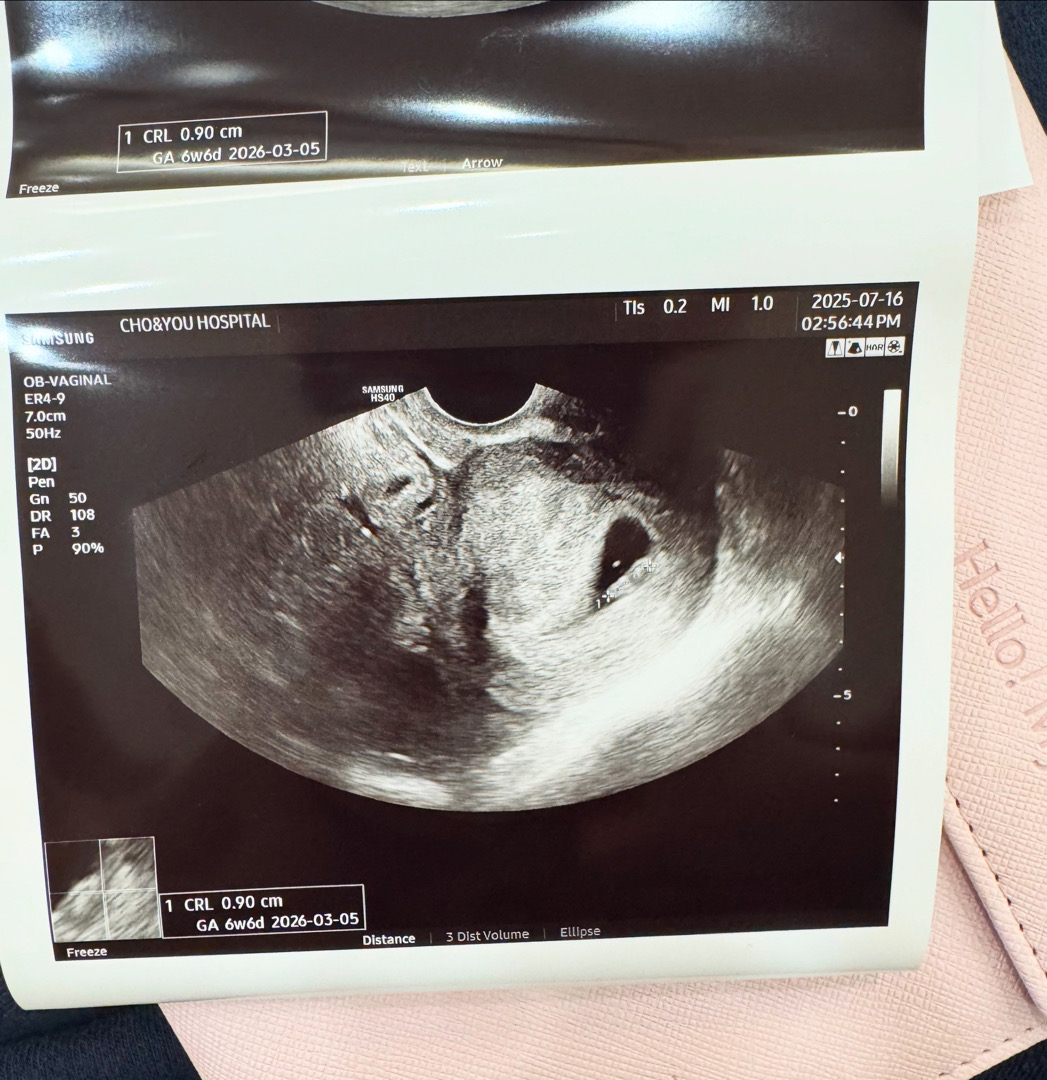

6주5일차 번데기 ㅋㅋㅋ 너무 귀여워요

입덧도 아직까진 없고 9미리래요 벌써부터 효자 울애기